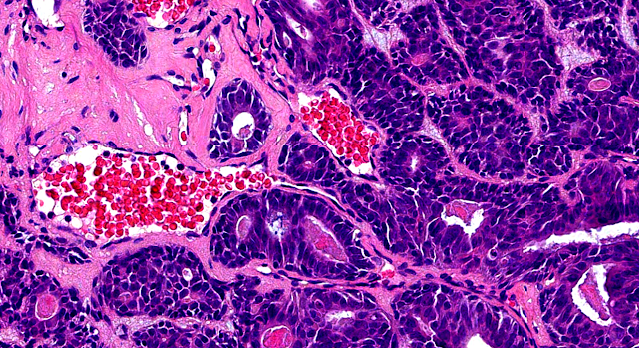

Dermatopathology Case 259 Get link Facebook X Pinterest Email Other Apps August 22, 2022 65-year-old male with a 3-month history of a mass involving the distal portion of the fifth finger on the right hand . Answer Get link Facebook X Pinterest Email Other Apps Comments